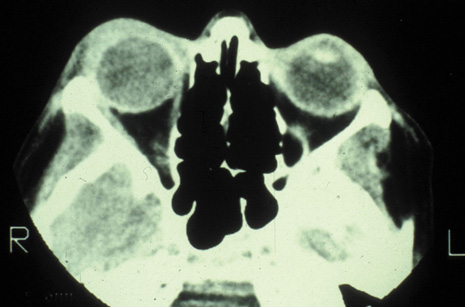

Fig. 23. Mucormycosis of the right ethmoidal sinus, with right orbital subperiosteal abscess formation. A. T1-weighted axial image. B. T2-weighted image. Note brain abscess.

CT shows sinusitis with or without bone destruction and is indistinguishable from other causes of orbital cellulitis.128 MRI may show carotid narrowing, occlusion, and absent flow in the superior ophthalmic vein (Fig. 24).72

Diagnosis is made by having a large index of suspicion and obtaining specimens of nasal turbinate, sinus, or infected orbital tissue. Large, branching nonseptate hyphae are readily apparent on hematoxylin and eosin staining or with methenamine silver staining (see Fig. 23). These hyphae can be grown on fungal culture.